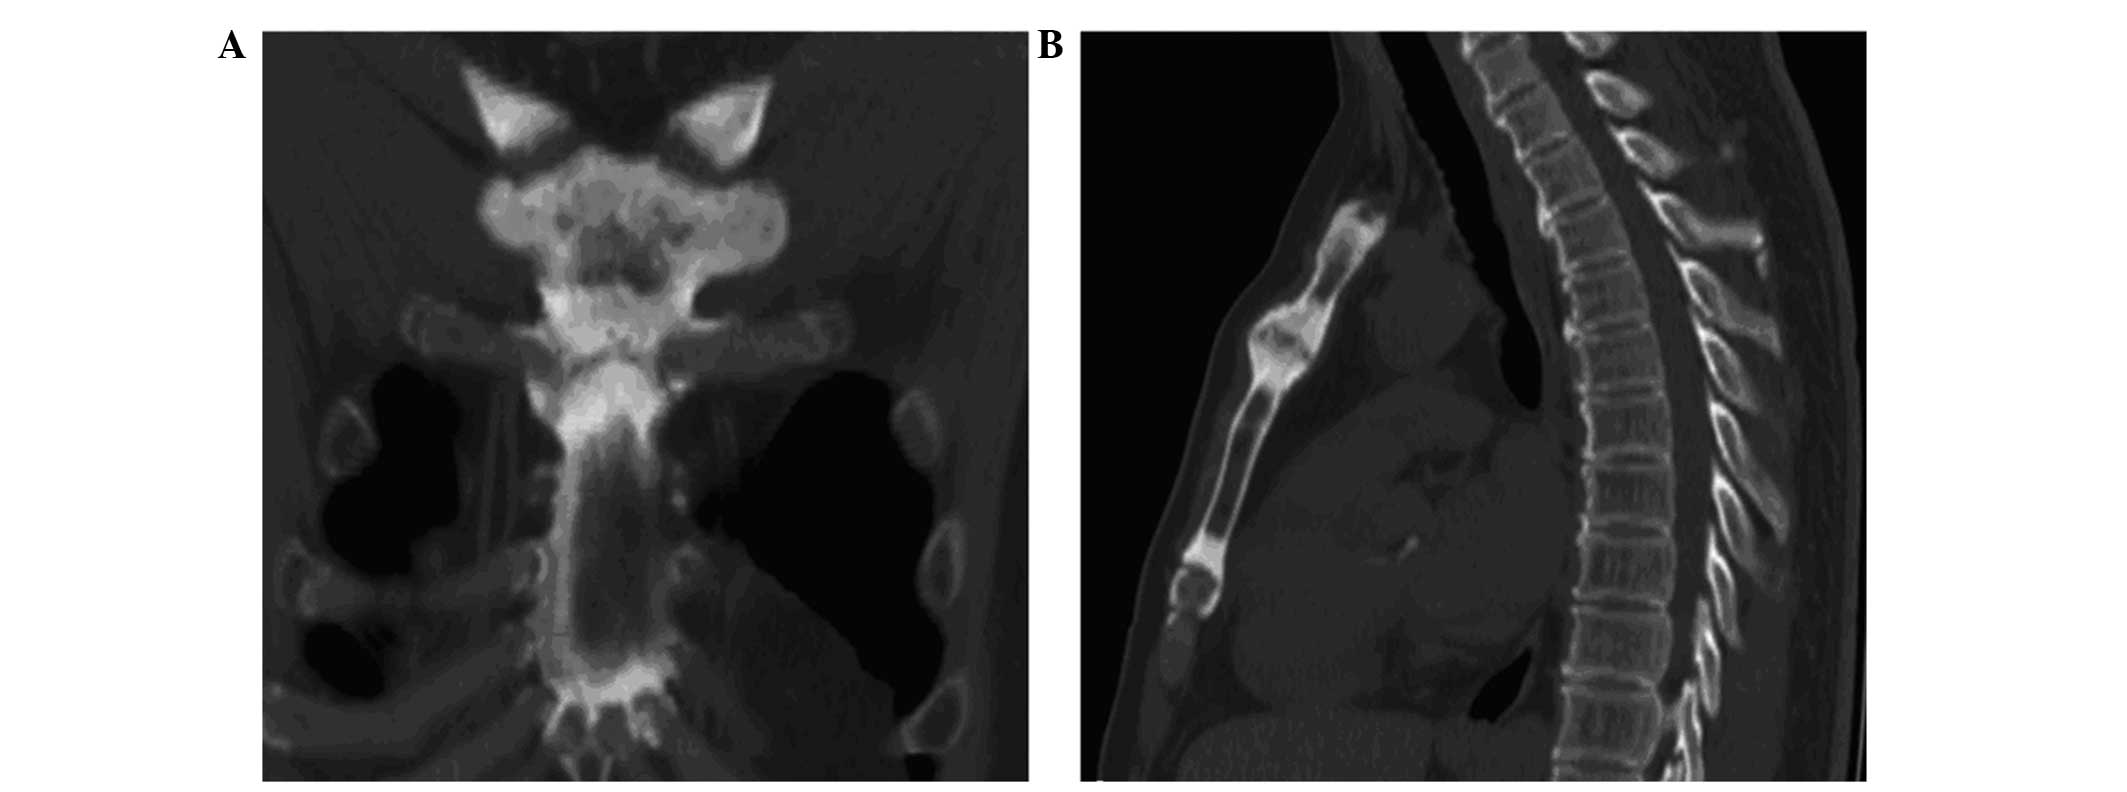

Whole-body 99m Tc methylene diphosphonate bone scintigram demonstrates increased uptake in both sternoclavicular joints the sternum the right greater trochanter. These diseases share some clinical radiologic and pathologic characteristics. It is composed of two portions separated by an articular disc of fibrocartilageThe bone areas entering into its formation are the sternal end of.

The sternoclavicular joint or sternoclavicular articulation is the joint between the manubrium of the sternum and the clavicle boneIt is structurally classed as a synovial saddle joint and functionally classed as a diarthrosis and multiaxial joint. B Bone scintigram obtained with technetium 99m 99m Tc medronate shows areas of increased radiotracer activity in the medial aspect of both clavicles arrows and in the. An entity initially known as chronic recurrent multifocal osteomyelitis was first described in 1972.

Especially the inspection of tonsillitis periodontitis and sinusitis is very important. These diseases share some clinical radiologic and pathologic characteristics. Joint Specific Conditions SAPHO Syndrome Middle-aged adults Skin changes ESRCRP mildly elevated Erosive changes Ossification of ligament insertion. Especially the inspection of tonsillitis periodontitis and sinusitis is very important. Treatment for focal infections. A Axial chest CT image shows marked hyperostosis osteosclerosis and ankylosis of the sternoclavicular joints arrows. SAPHO is an acronym for synovitis acne palmoplantar pustulosis hyperostosis and osteitis.